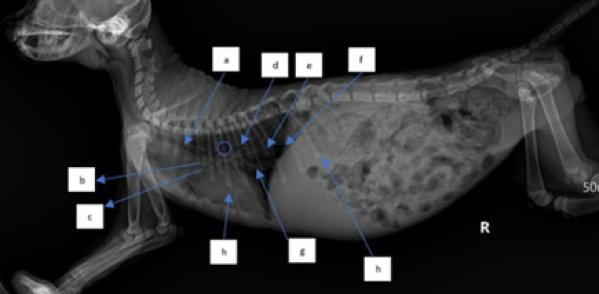

The outcomes of the X-ray investigation revealed the occurrence of discoloration in the abdominal cavity, accompanied by a noticeable progression in opacity. This phenomenon is commonly attributed to the emergence of fluid in the abdominal cavity (Figs. 2 and 3).

Fig. 3. Thoracic radiograph of Hiro’s cat in a lateral position with a dilated heart with an enlarged heart size. (a). Trachea, (b). cranial pulmonary artery, (c). pulmonary vein, (d). aorta, (e). pulmonary caudalis arteries and veins, (f). diaphragm, (g). vena cava caudalis, and (h). ascitic fluid.

The X-ray findings reveal a change in opacity in a section of the abdominal cavity, indicating an increase in radiopacity and the presence of ascites, or fluid buildup. Ultrasound imaging of the same area reveals anechoic regions between organs, which is a sign of fluid accumulation (Prajapati et al., 2022). Ascites are a symptomatic condition that occurs when fluid, both transudate and exudate, leaks into the space between the peritoneum and visceral layer of the abdominal cavity (Tilley et al., 2021). This is often a result of congestive heart failure or impaired venous flow and may cause cats to experience lethargy, abdominal distension, discomfort upon palpation, anorexia, vomiting, weight gain, scrotal or prepuce edema, and pain while lying down. Hypoalbuminemia, or low levels of albumin in the blood, is a contributing factor to ascites, as it reduces plasma osmotic pressure and increases vascular permeability, leading to fluid leakage from blood vessels into the abdominal cavity (Restijono et al., 2020).

Following changes occur in the caudal pulmonary arteries and veins or vascular patterns observed in the dorsoventral view of the X-ray position, specifically alterations in size. The pulmonary veins and arteries caudalis exhibit dilation, resulting in a vessel diameter larger than the IXth rib diameter, this is consistent with previous research, which states that enlargement of the left atrium and pulmonary veins is one of the symptoms of CHF in cats (Guglielmini and Diana, 2015; Bernes et al., 2020). The dilation of pulmonary arteries and veins is due to augmented pressure from systemic veins toward the right ventricle (Berry, 2010). The upsurge of pressure from systemic veins toward the right ventricle is caused by the improper blood circulation process in the right atrium and ventricle, leading to a small output of blood from the ventricles and the retention of blood in the heart chambers at the end of systole, which increases. This condition increases hydrostatic pressure, leading to the dilation of pulmonary arteries and veins (Triakoso, 2020). The high hydrostatic pressure causes fluid leakage from veins into pleural and peritoneal spaces, and potentially into pericardium and peripheral interstitial tissues. Ascites occur when fluid leakage surpasses the lymphatic system’s capacity (Tilley et al., 2021).